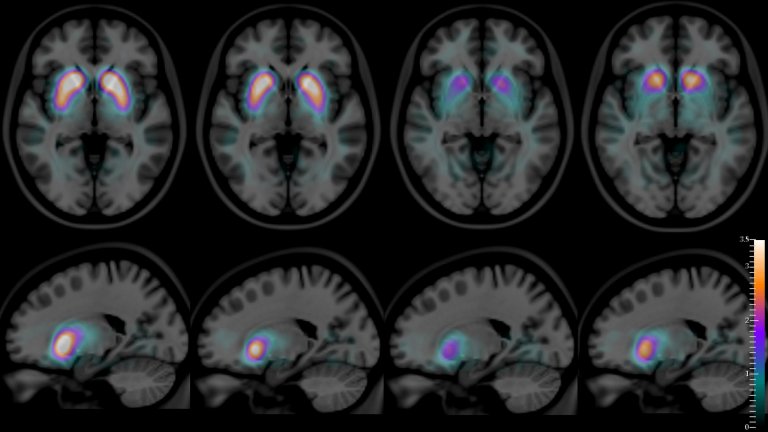

O diagnóstico é feito a partir de testes neuropsicológicos e exames de imagem. Diferente do Alzheimer, a demência por Lewy apresenta alterações específicas na dopamina, neurotransmissor essencial para o movimento e funções cerebrais.